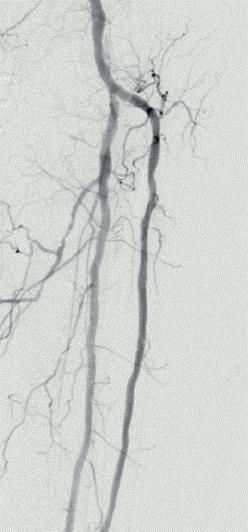

Multicentre experience shows “promising” midterm outcomes with IVL for calcified iliac occlusive disease

Shockwave intravascular lithotripsy (IVL) “expands endovascular strategies for iliac occlusive disease and can facilitate a ‘leave nothing behind’ approach,” Stefano Fazzini (Tor Vergata University, Rome, Italy) and colleagues write in an open-access Journal of Vascular Surgery (JVS) paper highlighting midterm outcomes from the IVLIAC registry—a multicentre, retrospective study of prospectively collected data.

“CALCIUM REMAINS A CHALLENGE IN the endovascular treatment of iliac artery disease, affecting both procedural and long-term outcomes,” Fazzini tells Vascular News. He goes on to comment that the standard approach of primary stenting, “although effective, is susceptible to stent recoil and under expansion in heavily calcified vessels” and notes that extensive calcification increases the risk of ruptures, especially when high-pressure balloons or balloon-expandable stents are used.

Fazzini also stresses that “no single stent is ideal for all calcified iliac lesions,” and that unnecessary stenting, especially at the bifurcation or when covering key branches, “can be avoided”.

In light of this, Fazzini et al set out to evaluate the midterm outcomes of patients with calcified iliac lesions treated with IVL, with or without adjunctive stenting, and to propose a new algorithm guiding these different treatment strategies.

The new algorithm, Fazzini explains, is based on lesion type (stenosis versus chronic total occlusion) and intraoperative functional assessments (extravascular ultrasound and pressure gradient) to determine whether stenting is necessary. “The impact

of sonic pressure waves improves vessel compliance and luminal gain, but such modifications may not always be evident on digital subtraction angiography alone,” he says, adding that intraoperative functional assessments play a “crucial” role in determining whether IVL alone is enough.

The investigators included all consecutive patients at four centres (Rome, Milan, Negrar and Trento) who underwent treatment with the Shockwave Medical peripheral IVL system for calcified iliac arteries from February 2021 to May 2024. Indication for IVL was Rutherford category of three or above in iliac lesions with moderate-to-severe calcification and was based on the new algorithm. The primary endpoint was primary patency, with assisted primary patency, secondary patency, and freedom from iliac complications also analysed.

Fazzini and colleagues share in JVS that a total of 100 iliac arteries were treated in 86 patients. They note that chronic limb-threatening ischaemia (CLTI) was present in 55% of patients, mean target lesion length was 40.95±29.25mm with a mean stenosis of 84±10%, and 12 of the lesions were chronic total occlusions. The authors report that technical

Target lesions were treated with

77%

IVL alone

23% IVL plus adjunctive stenting

success was 99% and that target lesions were treated with IVL alone in 77% of cases, whereas IVL plus adjunctive stenting was employed in the remaining 23% of the cases. They add that provisional stenting was performed in 11% of cases, while planned stenting was performed in 12%, and that mean residual stenosis was 14.95±14% at final angiogram. Primary patency and assisted primary patency at 24 months were 95% and 98%, respectively, while secondary patency was 100%. Primary patency showed no statistically significant difference between the IVL only and IVL plus adjunctive stenting groups.

“Shockwave IVL offers a safe and effective treatment option for calcific iliac occlusive disease,” the authors write in their conclusion. “This multicentre experience shows promising midterm results in terms of primary patency despite the very low stenting rate, preserving future treatment options.” They go on to stress that further studies are needed to confirm these findings.

Discussing the findings with Vascular News, Fazzini summarises that, in cases of severely calcified disease, “Shockwave IVL as a first-line strategy in iliac interventions allows for either the avoidance of unnecessary stenting or optimisation of stent expansion, both of which contribute to favourable midterm outcomes”.